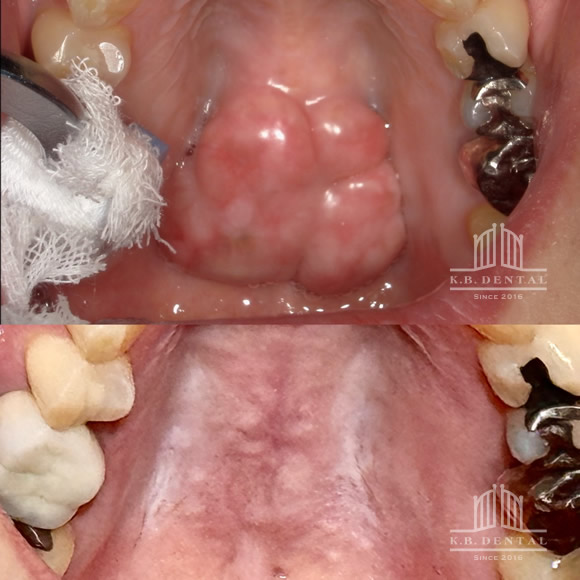

口蓋隆起(こうがいりゅうき)

口蓋隆起 症例1

口蓋隆起 症例2

口蓋隆起 症例3

歯の内側に発生したタイプの骨隆起です。静脈麻酔で約1時間半程度要します。